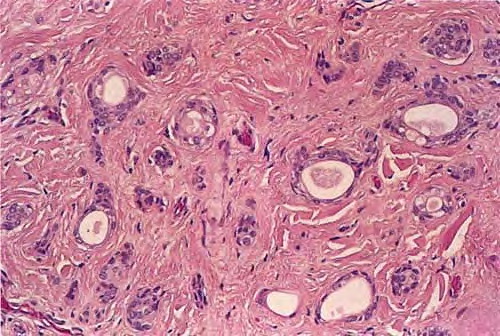

Syringoma = ورم غدي عرقي